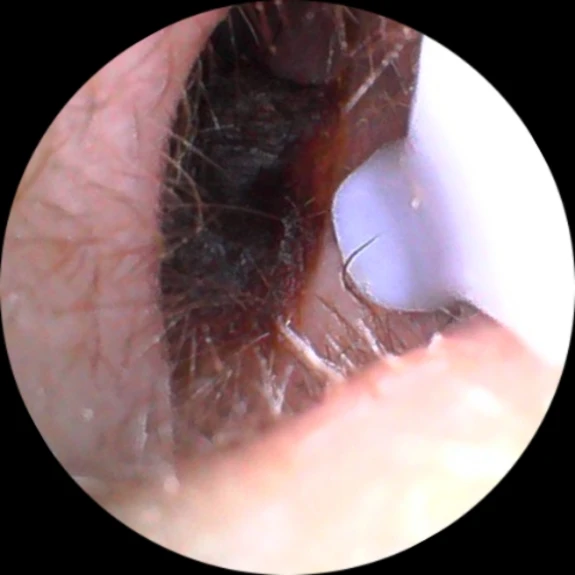

Domenic Grady J

Jarod Koss My recommendation for this device. Clear images and video, easy to use. Only the instructions are a little confusing. Open the app (i use useear from google play ), turn on the otoscope (5sec) and when the app asks to connect to wifi, go to the wifi section of your phone and among all available networks, aisee-xxx will appear. Connect to it and you have a transmission from the otoscope